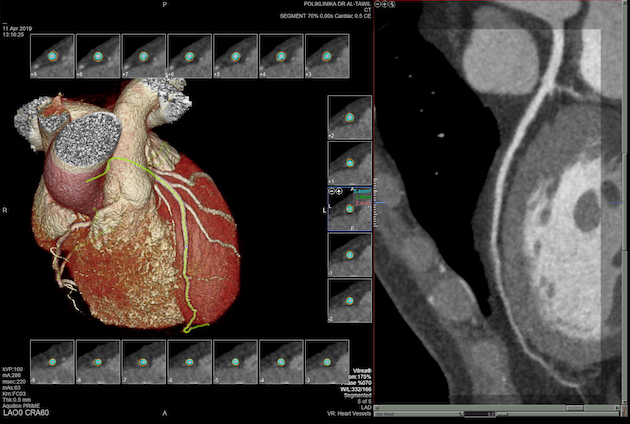

Također u slučaju pojave boli u prsima, gdje nema EKG promjena i lab.nalazi su uredni, radi se takozvani «triple rule-out» CT koronarografija-da bi se jednim pregledom isključila bolest koronarnih arterija, plućna tromboembolija ili disekcija aneurizme aorte, od kojih je svaka ponaosob potencijalno fatalna.

• MSCT koronarografija (prikaz krvnih žila srca CT-om, bez neugodnosti i komplikacija koje nosi klasična koronarografija), uz paralelan prikaz pluća te grudne aorte.